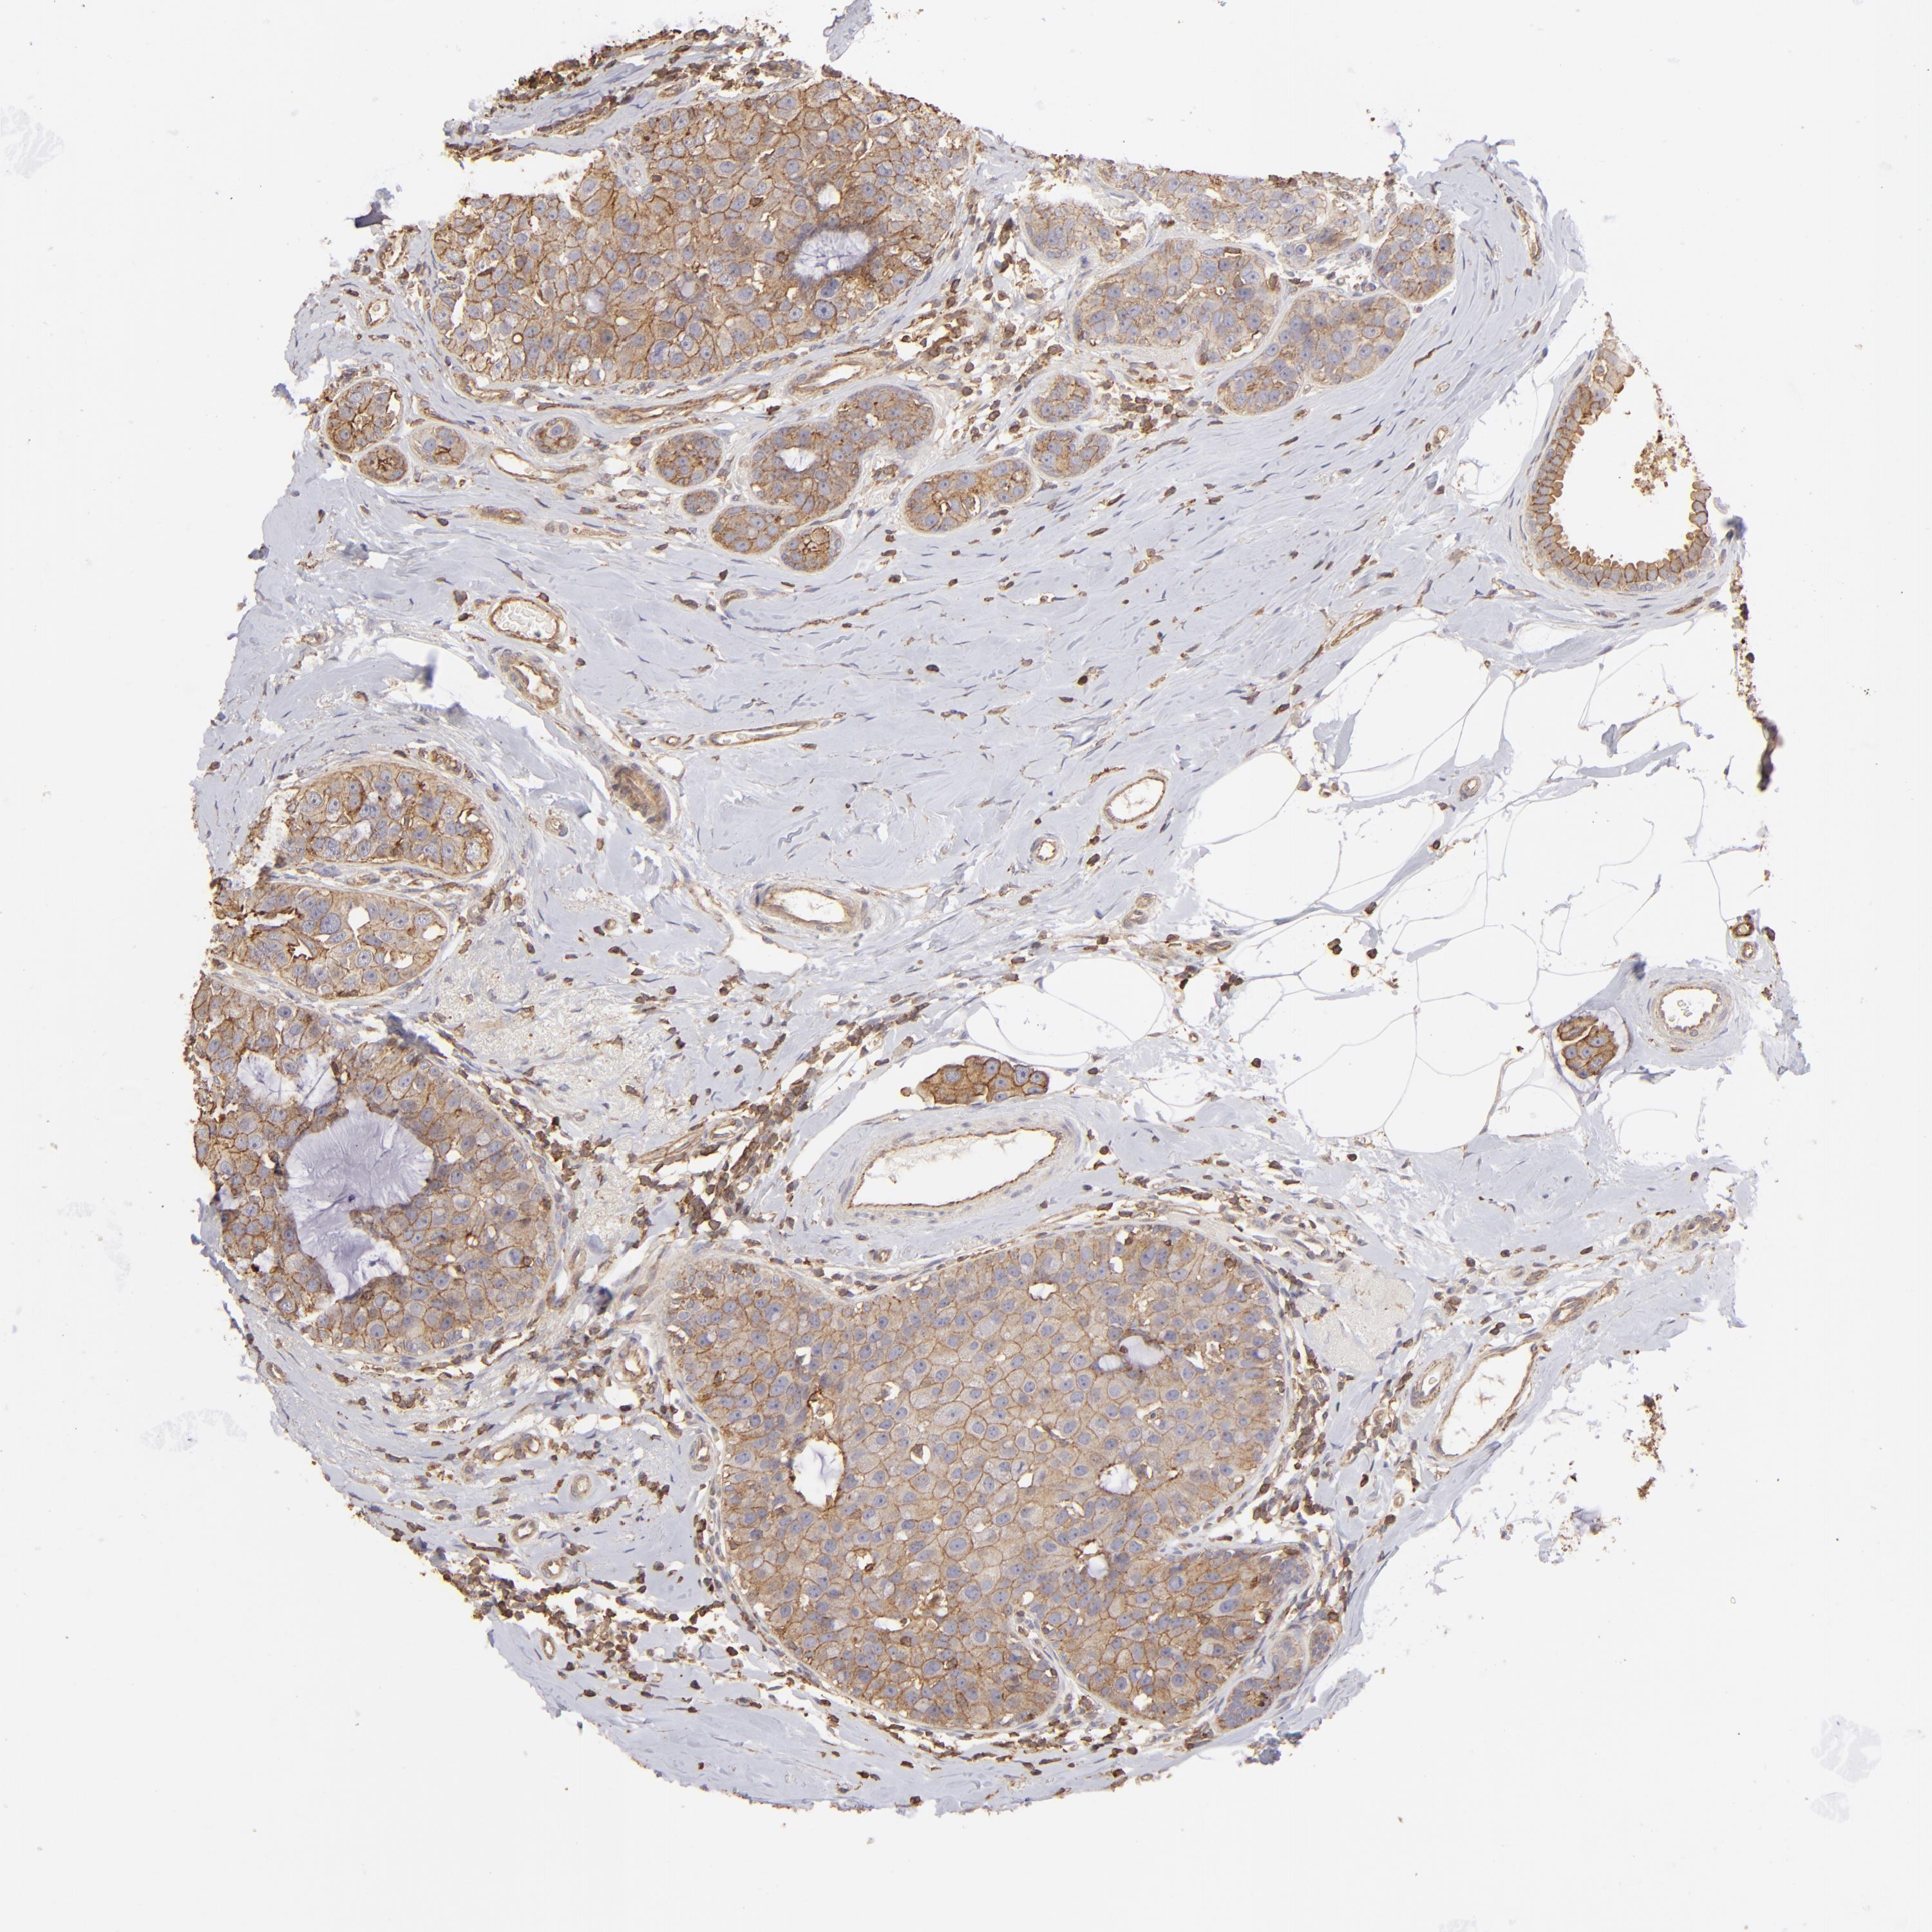

BRCA TCGA BRCA VALIDATION PROTEIN EXPRESSION

ANTIBODIES

AND

VALIDATION